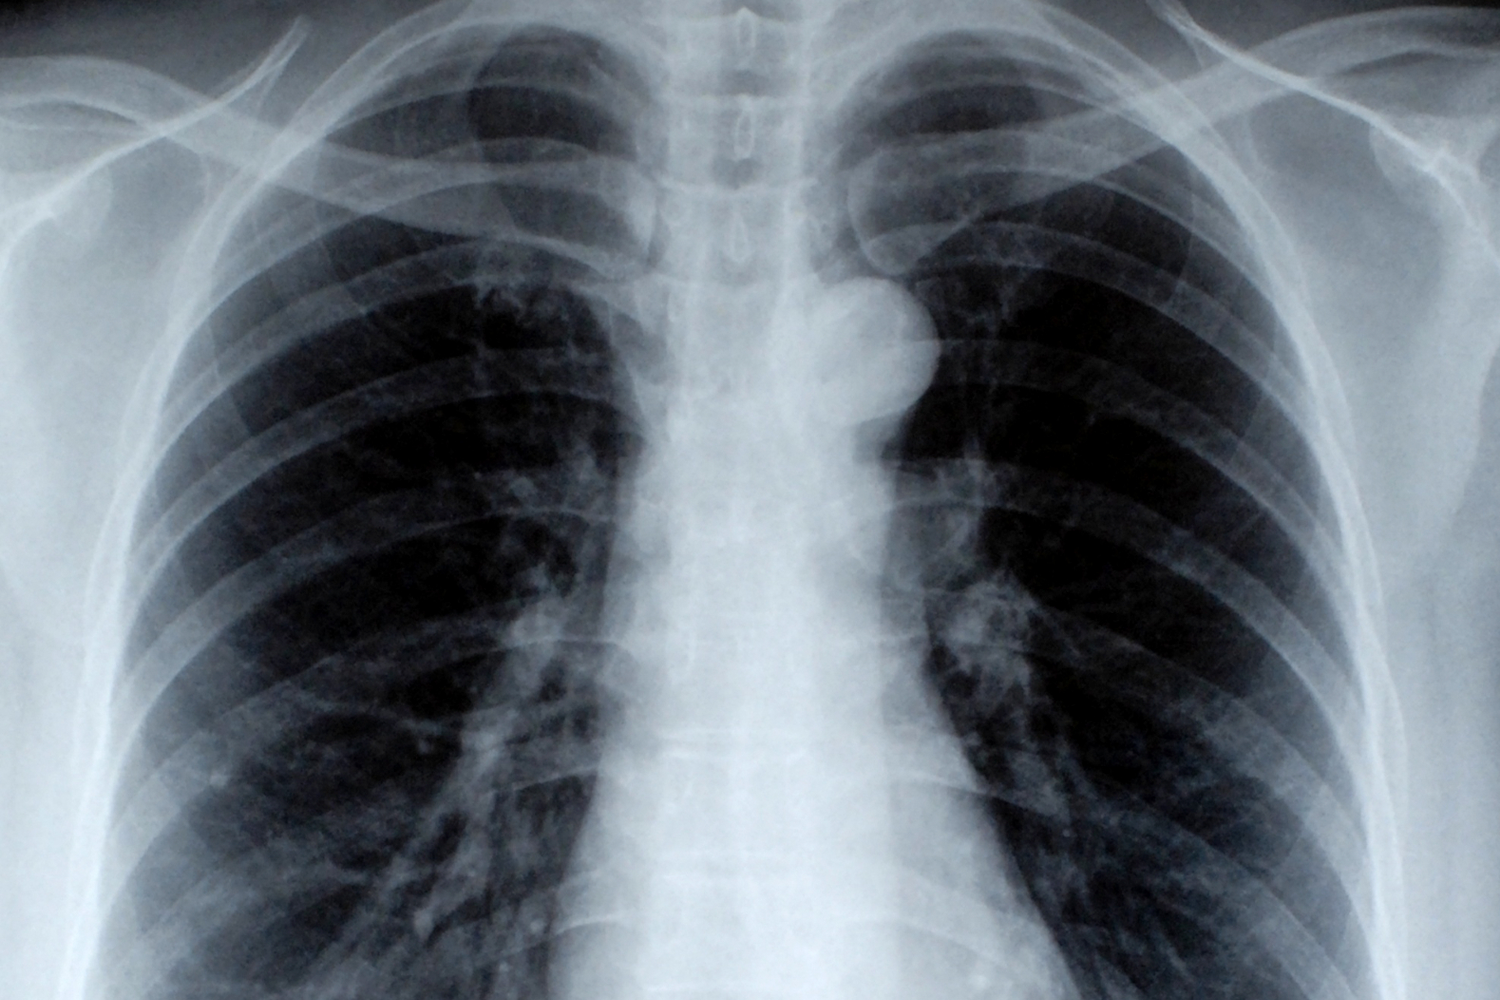

Los rayos X son un examen de diagnóstico por imágenes que utiliza radiación electromagnética para capturar imágenes del interior del cuerpo. Al pasar a través del cuerpo, los rayos X son absorbidos en diferentes grados por los tejidos, creando una imagen en blanco y negro en función de la densidad de los materiales atravesados.

Rayos X